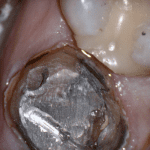

This case was scanned by two different scanners. Once by the Medit i500 and another time with the Aoralscan. Both the meshes are included so you can compare the two. It was scanned to deliver a case that retrofits a partial denture